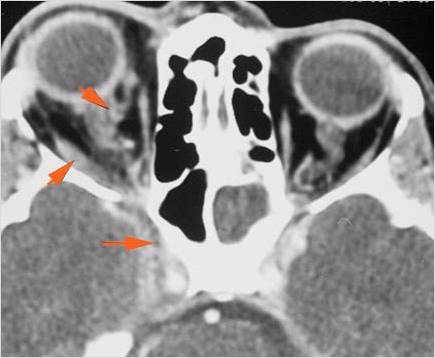

The extraconal orbital fat is abnormal. [Yes/No]

There is a subperiosteal abscess or edema along the medial wall, roof or floor of the orbit. [Yes/No]

The intraconal orbital fat is infiltrated. [Yes/No]